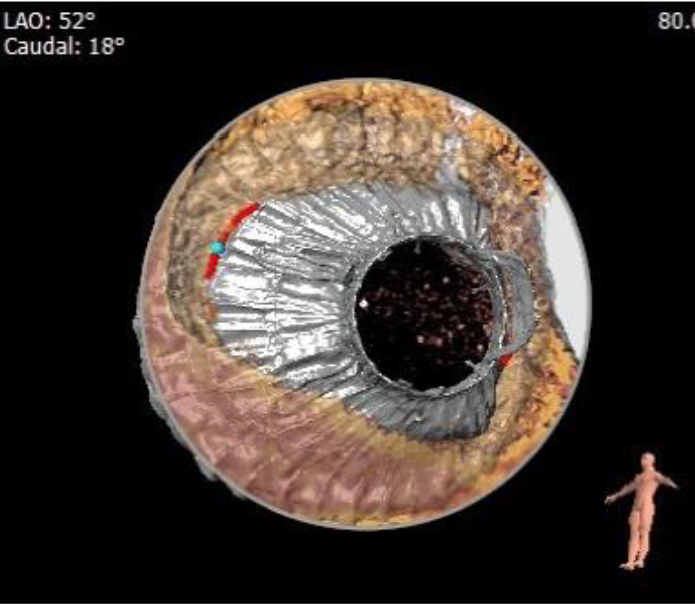

术前CT评估资料

根据术前CT的测量结果,选择使用JS/TTVI28-55号的LuX-Valve®瓣膜。